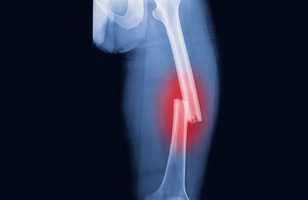

شکستگی استخوان به وضعیتی اطلاق میشود که در آن استخوان به دلایل مختلف از جمله ضربه، فشار یا شرایط بیماریزا مانند پوکی استخوان، شکسته شود. شکستگیها بر اساس نوع آسیب و محل آن به دستههای مختلفی تقسیم میشوند:

شکستگی عرضی: استخوان به صورت افقی شکسته میشود.

شکستگی طولی: شکستگی به صورت عمودی یا مایل رخ میدهد.

عکسبرداری با اشعه ایکس: یکی از رایجترین و دقیقترین روشها برای تشخیص شکستگی است.